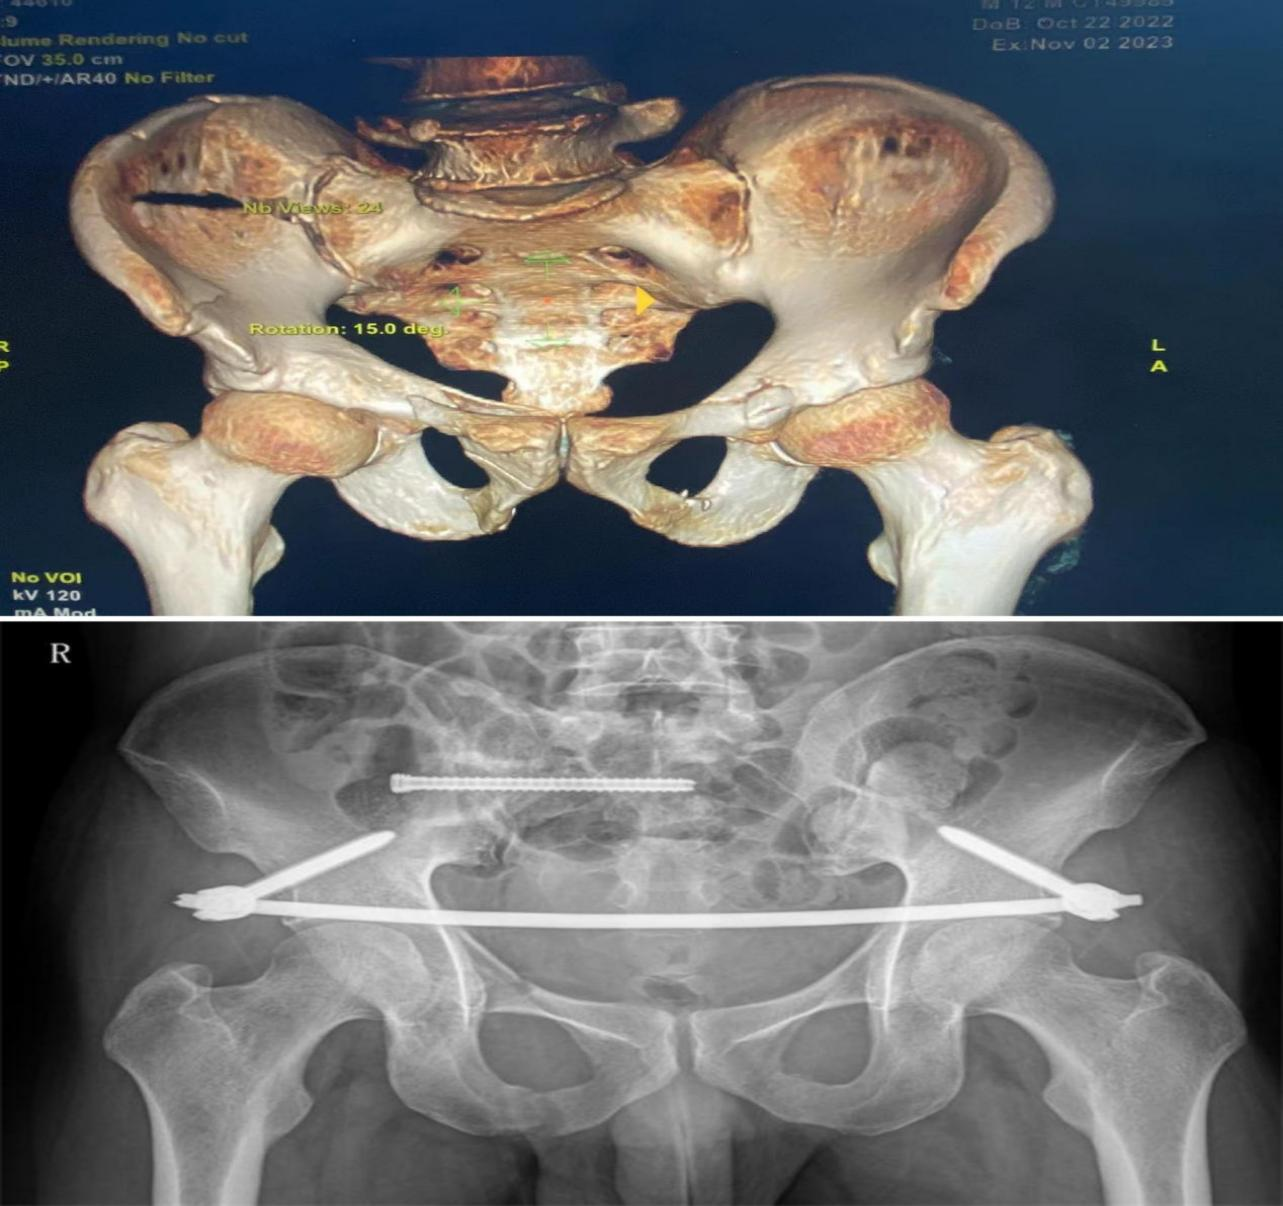

據(jù)了解,菏澤醫(yī)專(zhuān)附屬醫(yī)院骨外科目前開(kāi)展的股骨頸骨折FNS內(nèi)固定術(shù)、股骨粗隆間骨折PFBN內(nèi)固定術(shù)、骨盆骨折微創(chuàng)骶髂螺釘+infix內(nèi)固定術(shù)、骨盆骨折LC-2螺釘內(nèi)固定術(shù)、胸腰椎骨折經(jīng)皮椎弓根螺釘內(nèi)固定術(shù)、肩鎖關(guān)節(jié)脫位袢鋼板內(nèi)固定術(shù)、跗骨竇入路治療跟骨骨折、彈性髓內(nèi)釘治療兒童骨折、兒童肱骨髁上骨折閉合復(fù)位克氏針內(nèi)固定術(shù)、關(guān)節(jié)鏡下半月板修復(fù)、滑膜切除、脛骨髁間嵴骨折內(nèi)固定、肩袖撕裂修補(bǔ)等手術(shù)均是微創(chuàng)化手術(shù),不僅如此,在脊柱治療方面,骨外科開(kāi)展了UBE脊柱微創(chuàng)手術(shù),有效治療了椎間盤(pán)突出癥、椎管狹窄癥等疾病。此外,醫(yī)院還與著名矯形外科專(zhuān)家秦泗河成立“秦泗河名醫(yī)工作室”,是山東省殘聯(lián)指定菏澤唯一殘疾兒童矯形定點(diǎn)醫(yī)院?!肮峭饪婆c上級(jí)醫(yī)院聯(lián)系緊密,常年邀請(qǐng)國(guó)家級(jí)、省級(jí)專(zhuān)家來(lái)院坐診、手術(shù)?!?/span>孫全波介紹。

骨盆骨折術(shù)前術(shù)后對(duì)比